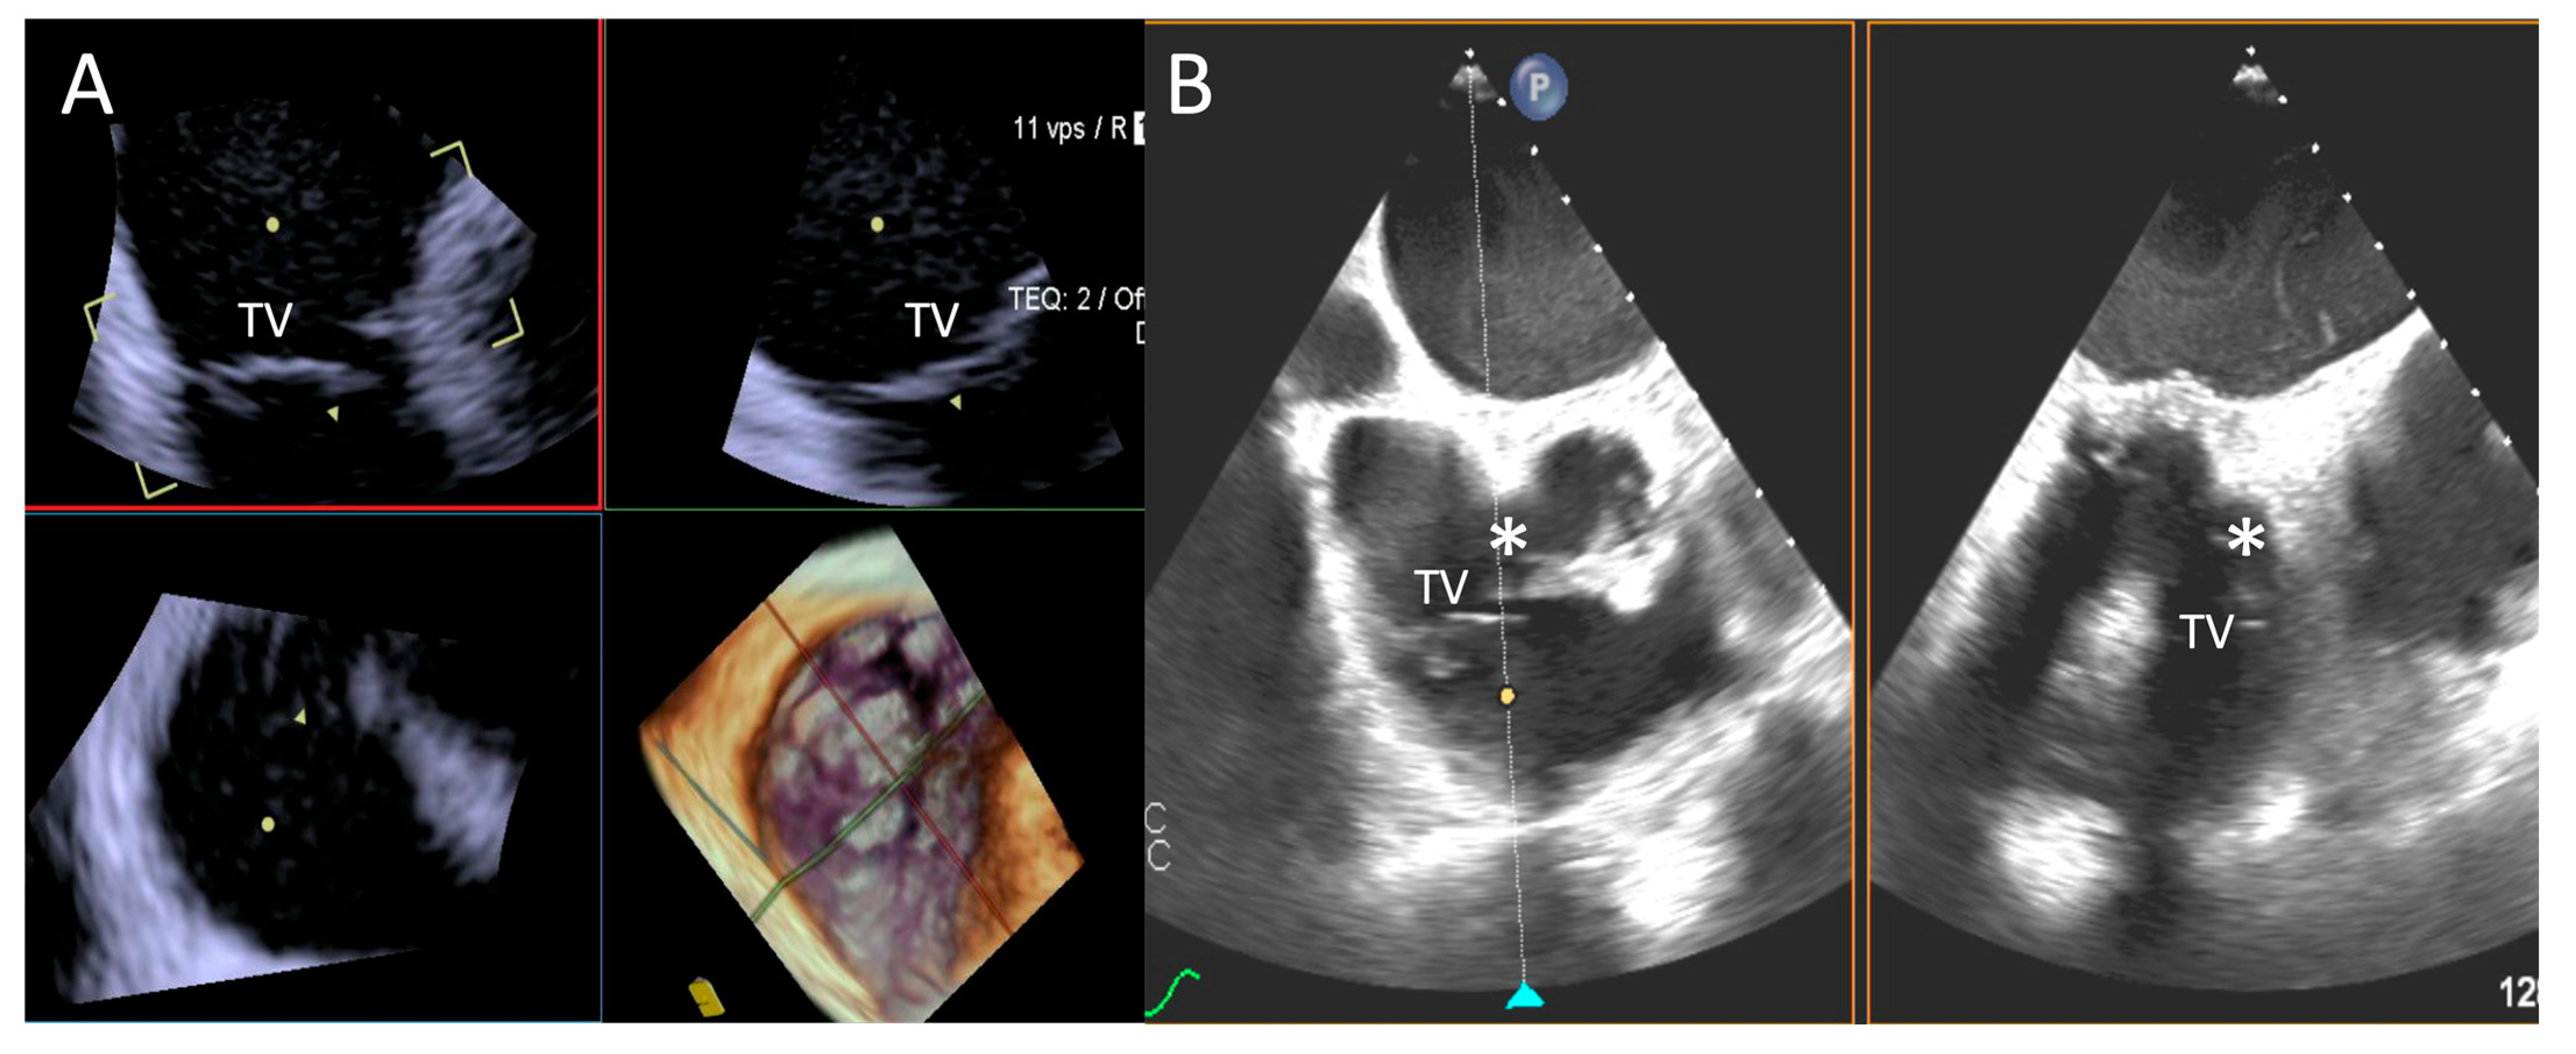

- Step number 2: identification of the target lesion.

3.3.1. Step-by-Step Evaluation